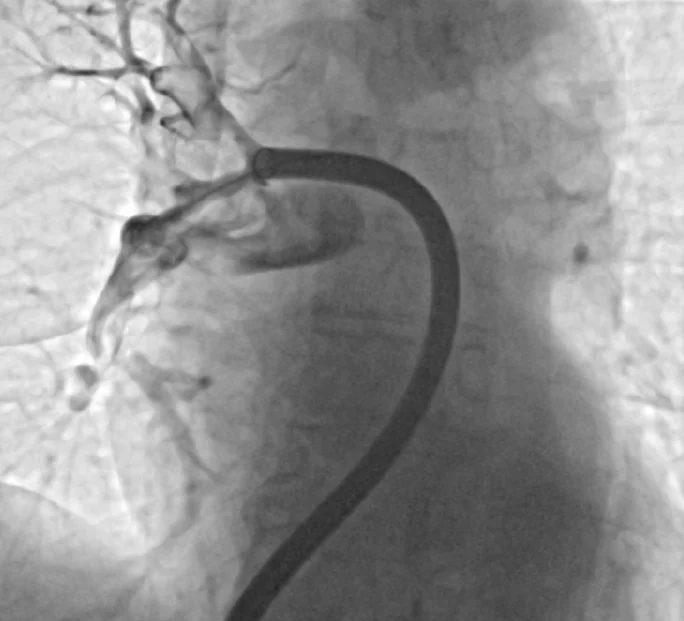

Doslej je zdravljenje temeljilo predvsem na antikoagulantnih zdravilih (proti strjevanju krvi), ki preprečujejo rast strdka, v hujših primerih pa na trombolitični terapiji, ki strdek raztopi, a hkrati poveča tveganje za krvavitve. Novejši pristop predstavlja mehanska odstranitev strdka s katetrom, pojasnjujejo v SB Murska Sobota. Gre za minimalno invaziven poseg, pri katerem zdravnik skozi veno, običajno v dimljah, uvede kateter in ga pod rentgenskim nadzorom vodi do mesta zapore. Strdek nato s posebnim sistemom odstrani z ustvarjanjem podtlaka ali mehanskim zajemom. Gre v vsakem primeru za zelo pomemben napredek v zdravljenju žilnih bolezni.